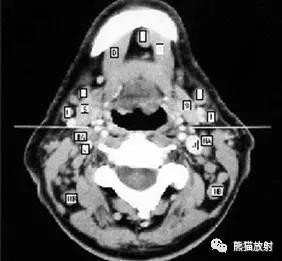

颈部淋巴结呈软组织密度,类圆或卵圆形,正常时短径小于5mm。

颈部淋巴结分为七区:

I区:颏下及颌下淋巴结

II区:颈内静脉链上组

III区:颈内静脉链中组

IV区:颈内静脉链下组

V区:颈后三角区淋巴结,即胸锁乳突肌后缘、斜方肌前缘及锁骨构成的三角区内的淋巴结

VI区:中央区淋巴结,包括喉前、气管前和气管旁淋巴结

VII区:上纵隔淋巴结